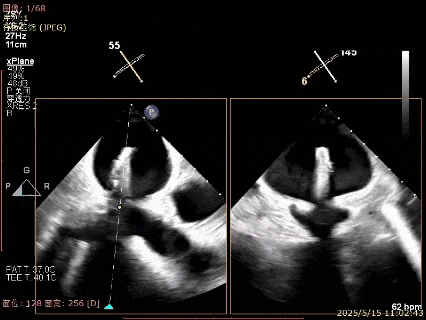

Bicomm切面看3区脱垂累及内交界

上Color,可见反流主要来自于3区

X-Plane切面切1区未见明显异常

1区上Color,未见反流来源

X-Plane切面切2区未见明显异常

2区上Color,未见反流来源

X-Plane切面切3区可见后叶脱垂

3区上Color,可见反流来源

X-Plane切面切内交界可见脱垂

内交界上Color,可见反流来源

3D Enface 3区后叶脱向左房累及内交界

3D Enface 可见反流由后向前由内向外冲出